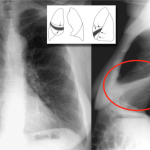

RIGHT MIDDLE LOBE ATELECTASIS

The archive below organizes different examples of a left middle lobe atelectasis. It will really be the anatomical location of the finding that will help diagnosis this SPECIFIC subtype of atelectasis. Whats more, this type of atelectasis often obscures the right cardiac border. Click on the thumbnails below to view the archive.